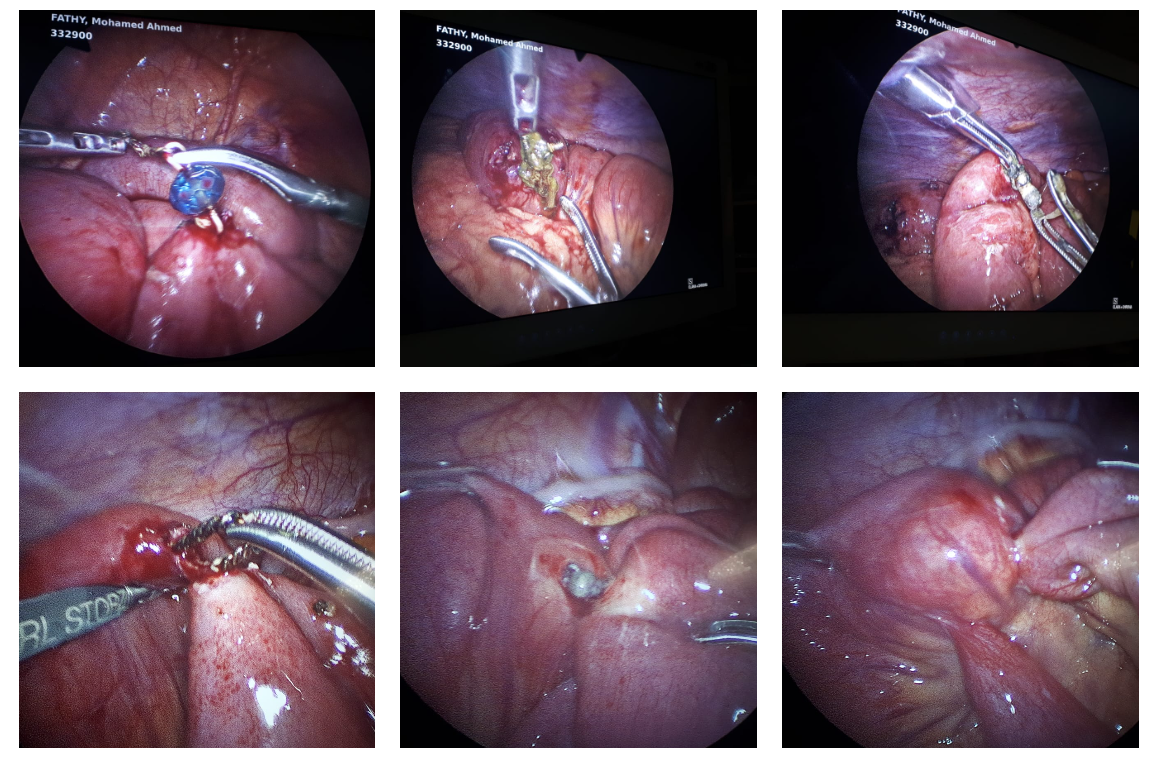

A 13 year old girl has been successfully treated by total Laparoscopic excision of type 1 –C Choledochal cyst and hepatico-duodenostomy . She has been having recurrent abdominal pain, post feeding discomfort, nausea, occasional fever and vomiting. After thorough evaluation a large type 1c Choledochal cyst associated with hepatosplenomegaly was diagnosed. After preparation, Laparoscopic excision and bilio-enteric anastomosis was carried out. She had highly vascular and thick fibrotic cyst wall with adhesions due to multiple cholangitic attacks. The surgery could be completed completely Laparoscopically with minimal blood loss. Child had a very comfortable post operative recovery, starting oral feeds 48 hours after surgery with excellent cosmetic outcome.

Currently minimally invasive technique is being the procedure of choice for such complex anomalies with excellent outcomes.